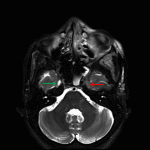

- Asymmetric hypoenhancement of the left superior ophthalmic vein and left cavernous sinus

- Cavernous sinus thrombosis

Findings highly concerning for invasive fungal sinusitis with sinus disease involving the left sphenoid sinus, left greater than right maxillary sinuses, and bilateral ethmoid air cells and contiguous extension with left preseptal and postseptal orbital cellulitis, cellulitis/myositis involving the left masticator and parapharyngeal spaces, and evidence of intracranial extension with left superior ophthalmic vein and left cavernous sinus thrombosis. No peripherally enhancing collection to suggest abscess. No convincing enhancement of the left ophthalmic artery is concerning for thrombosis, which could be further evaluated with CTA or catheter angiography. Recommend urgent surgical consultation.